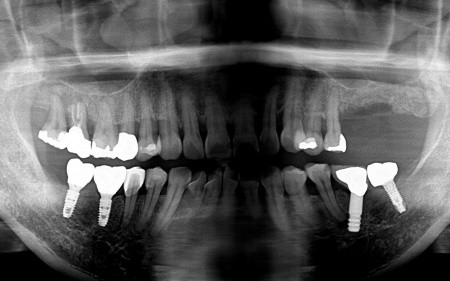

50代女性 温存が難しい奥歯を抜いてインプラントで噛み合わせを回復した症例

拝見したところ、左上の抜歯部周辺は歯を支える骨が溶ける「骨吸収」が進行し、隣接している歯を含めた複数の歯がひどくグラグラしており、温存が困難です。

噛み合わせも安定していなかったため、このままでは残っている歯への負担が増加し、歯の揺れやさらなる噛み合わせの悪化につながるリスクがあります。

また、右下奥歯には、両隣の歯を土台にして橋を渡すように欠損部を補う被せ物「ブリッジ」が装着されていました。

右下奥歯は2本欠損しており、親知らず(第3大臼歯)と手前の奥歯(第2小臼歯)の2本でブリッジを支えていますが、これは親知らずに過度な負荷がかかる構造です。

親知らずはすでに大きく傾いており、こちらも温存が難しいため、ブリッジを除去してから親知らずを抜く必要があります。

以上のことから、ブリッジの除去と併せて、温存が難しい左上奥歯2本と右下の親知らず1本を抜き、欠損部位を補う治療を検討する必要があると診断しました。